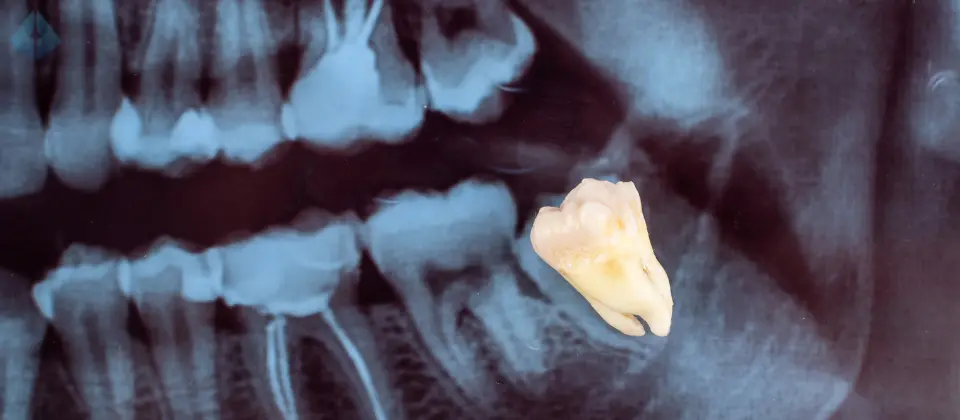

Noticed your teeth shifting? Preventive Wisdom Teeth Removal is key to protecting your smile. Discover Dr. Carranza’s expert approach in Westfield, NJ.